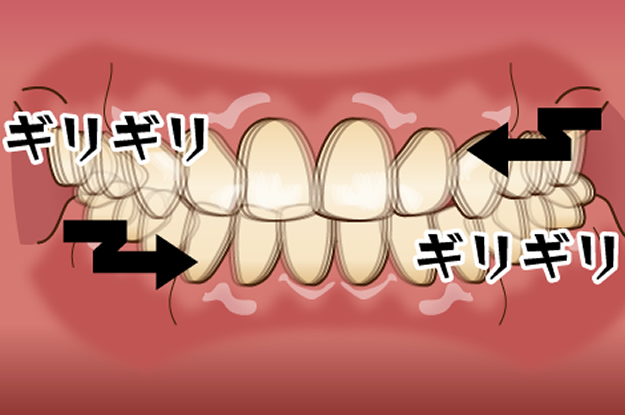

グラインディング(歯ぎしり)

良く一般的に歯ぎしりと言われるもので、上下の歯をこするタイプで、ギリギリと音が出ます。クレンチング(食いしばり)